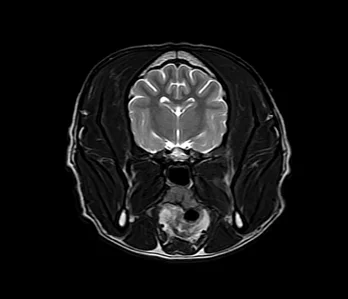

• MRI

영상의학과는 X-ray, 초음파, CT, MRI 등 다양한 첨단 장비를 활용하여 동물의 내부 상태를 영상으로 표현하고, 이를 기반으로 정확한 진단과 치료 방향을 제시하는 역할을 합니다.

하지만 영상 장비만으로 모든 것이 해결되지는 않습니다. 장비의 수준과 함께, 이를 해석하고 판단하는 영상의학 전문 수의사의 경험과 실력이 무엇보다 중요합니다.

• MRI 케이스 수 : 8천건 이상

다년간 다수의 케이스를 다룬 영상진단 전공 수의사들이 직접 판독 및 진단하며, 정확한 진단은 곧 효과적인 치료로 이어집니다.